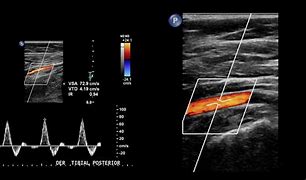

Pruebas complementarias. Eco-Doppler: se observa velocidad claramente disminuida en comparación con la contralateral a nivel poplíteo y pedio. Sospecha de trombosis paraneoplásica.

Hallazgos ecográficos

El uso de ecografía en atención primaria y urgencias puede ser muy útil para ayudarnos en el diagnóstico como para confirmar nuestra sospecha inicial. En este caso nos confirmó claramente una isquemia arterial, enviando el paciente sin perder tiempo directamente a un hospital de tercer nivel, donde se completó el estudio y se procedió a escoger la técnica más apropiada para nuestro paciente concreto. Nuestra sospecha inicial se confirmó posteriormente a pesar de nuestras posibles dudas y lo errático de la clínica y las evaluaciones previas.